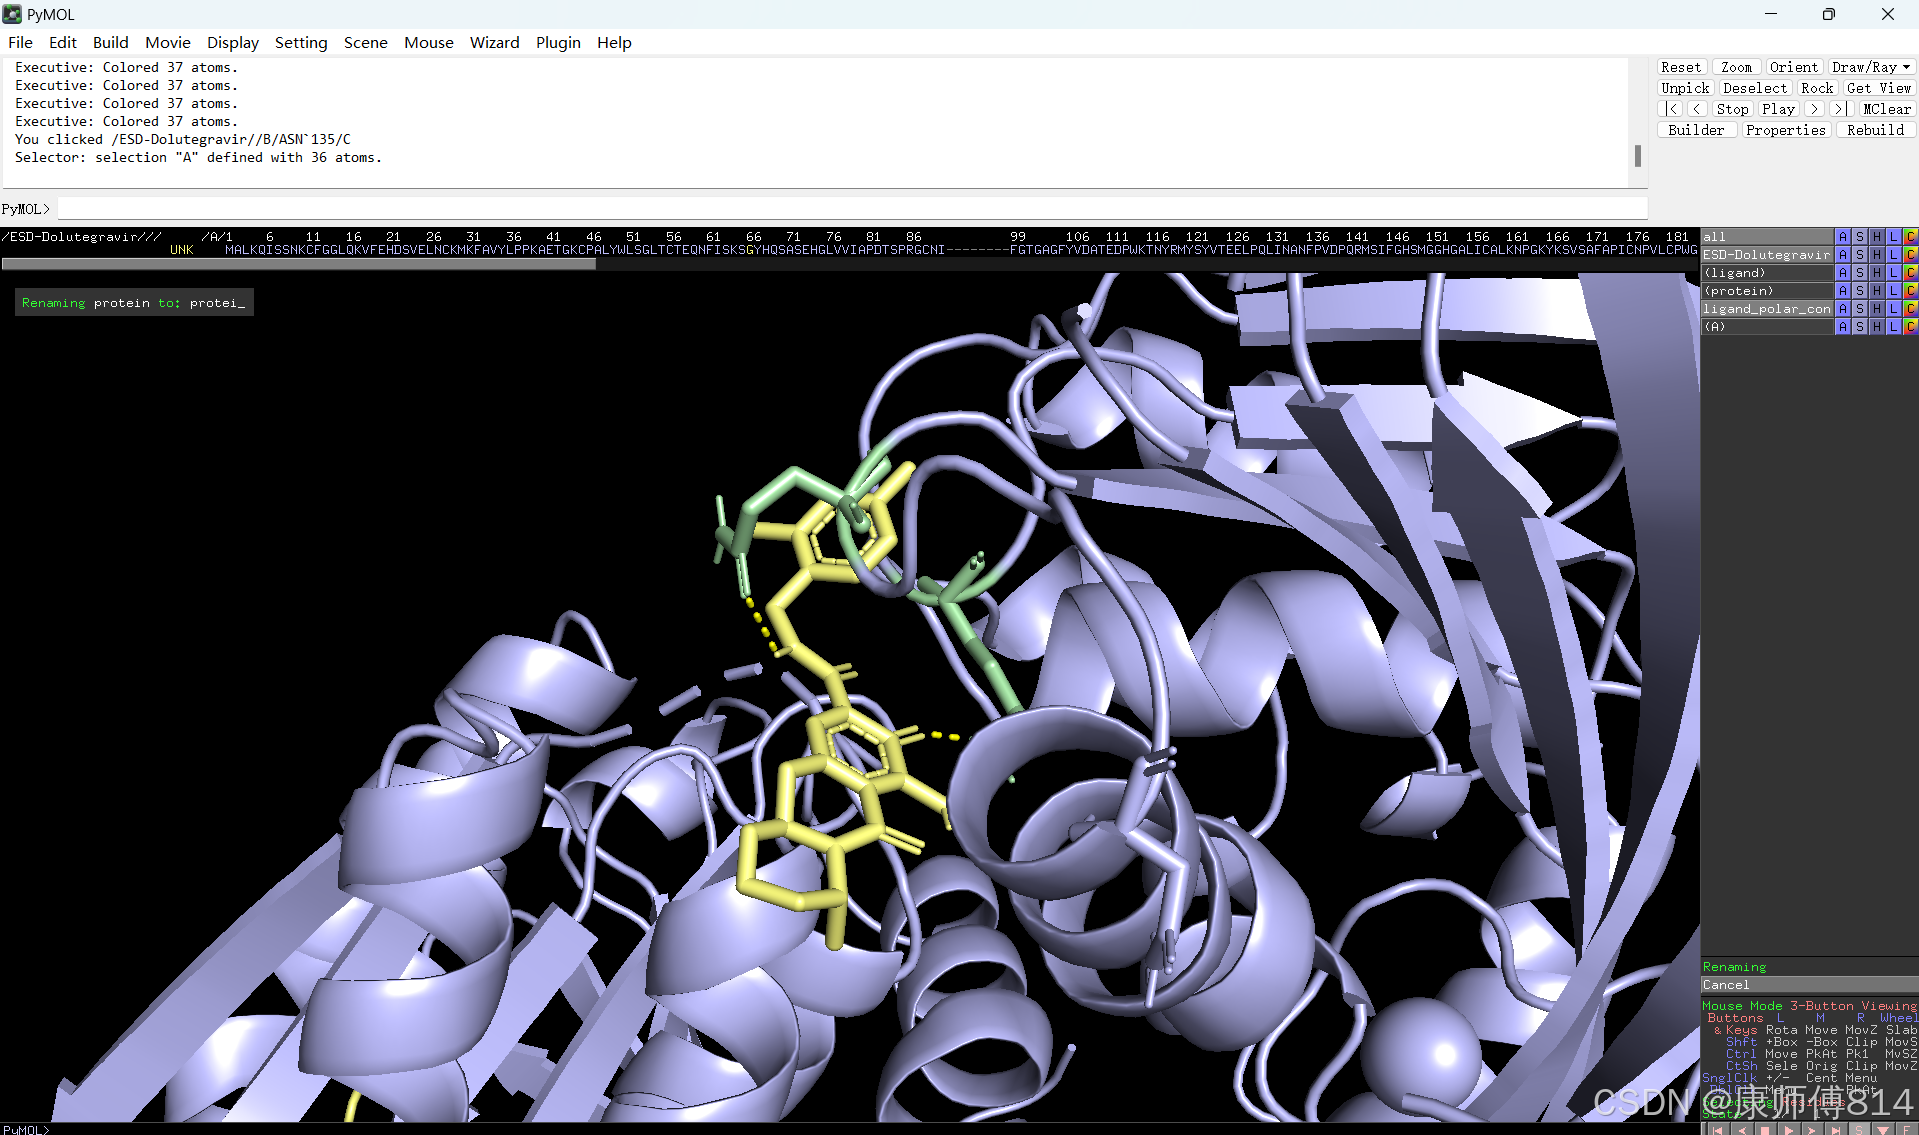

#接下来打开pymol操作

#在pymol中打开刚才得到的pdb文件,点击右下角S打开序列,选中小分子序列,命名为ligand。

#同样选中蛋白质序列,先将右下角Selecing选为Chains,然后才能悬着呢全部蛋白质序列(如果是多聚体蛋白,按住shift以连续选中多条链),命名为protein

#点击蛋白和小分子后的C按钮可以修改颜色

#选中小分子,按以下顺序点击以显示结合位点的氢键

#选中蛋白,点击show-sticks显示氨基酸棍状结构,右下角Selecting修改为Residues模式,选中与小分子连接的氨基酸残基,命名为A,并更改颜色

#点击蛋白,点击H-sicks隐藏蛋白棍状结构,然后显示小分子结合位点氨基酸残基棍状结构

#此时展示分子对接的基本要素已经形成,后续可根据需要修改背景颜色、显示氨基酸残基名字以及氢键键能等等,这里不再赘述

结果演示